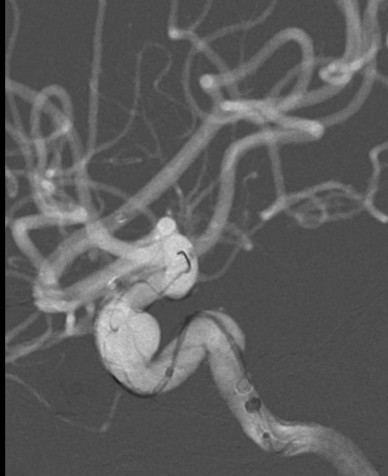

正侧位造影示动脉瘤内造影剂明显滞留,载瘤动脉通畅,血流导向作用显著。

术后即刻:

术后6个月复查动脉瘤完全闭塞,局部血管重建。